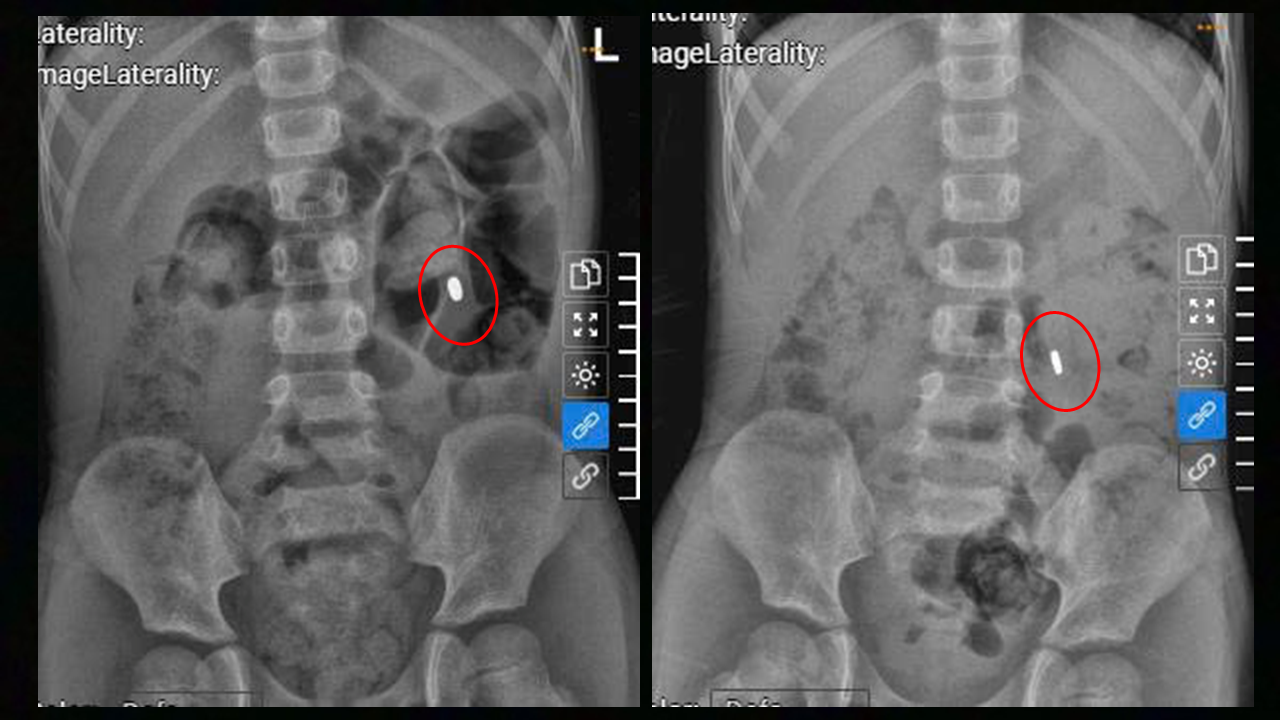

The magnetic mass in the patient's abdomen before and after laxative use. Photo: Tam Anh General Hospital |

After 4 days of medication, the magnetic mass moved into the small intestine but had not yet passed. Doctors adjusted the medication dosage, and fortunately, the foreign object was expelled, saving the child from surgery.